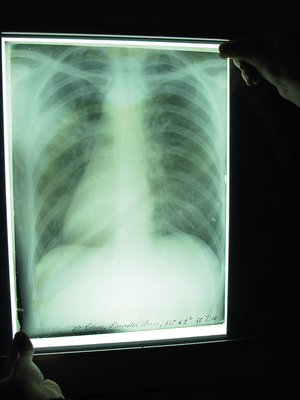

Thorax-Röntgenbild auf einer mit Gelatine-Bromsilber-Lösung beschichteten Glasplatte (1914) | © E. Flom

Ich unterrichte das Lehrfach Strahlentherapeutische Technik an der MTA-Schule am Universitätsklinikum Düsseldorf. Die MTA-Schule hat sich in den vergangenen drei Jahren stark verändert. In allen Klinikbereichen des Universitätsklinikums fehlen MTA-Mitarbeiter/ -innen. Deshalb investiert das Uniklinikum mehr Geld für zusätzliche, neue Lehrerstellen zur Stärkung der Ausbildung. Seit Herbst letzten Jahres werden unter anderem wieder MTA-F (Medizinisch-Technische/r Assistent/-in für Funktionsdiagnostik) ausgebildet. Darüber hinaus wird auch das Schulgebäude saniert, um mehr Unterrichtsräume zu gewinnen. Bei diesen Arbeiten haben wir in einem solchen renovierungsbedürftigen Raum mehrere Kartons entdeckt – augenscheinlich normale Kartons von Röntgenfilmen. Überraschenderweise enthielten diese Kartons uralte, mit Gelatine-Bromsilber-Lösung beschichtete Glasplatten mit Röntgenaufnahmen. „Röntgenphotographien“ – so hat man diese Bilder vor 100 Jahren genannt. Es handelt sich dabei um mehr als 50 Glasplatten, überwiegend 30 x 24 cm2 groß, mit dem Aufnahmedatum, Namen und Alter des Patienten. Die Bilder auf den Röntgenplatten sind zwischen 1909 und 1921 entstanden und zeigen überwiegend Darstellungen des Thorax-(Brustkorb-)Bereiches. Auch die ehemalige, pensionierte Schuldirektorin Monika Schmidt kannte auf Nachfrage den Ursprung dieser Bildplatten nicht. Dabei ist die Schule selbst schon circa 60 Jahre alt.

Ach, Entschuldigung! Es waren damals noch keine MTA. Sie wurden „Röntgenschwestern“, „Spezialschwestern“, „Röntgenassistenten“ genannt – diese Berufsbezeichnung war damals üblich. Wir haben die Platten zuerst katalogisiert und dank Prof. Dr. med. Gerald Antoch, Direktor des Instituts für Diagnostische und Interventionelle Radiologie und in seiner fachlichen Zuständigkeit, auch Ärztlicher Leiter der MTA-Schule, befunden können. Das waren zwei wertvolle Unterrichtsstunden von Prof. Antoch unter der aktiven Mitarbeit von Schülern/-innen, nicht zu vergessen die hervorragende Arbeit von denjenigen, die diese Röntgenaufnahmen angefertigt haben. Gemeint ist hier die ausgezeichnete Qualität dieser Aufnahmen, die auch selbst nach 100 bis 110 Jahren noch sehr gut ist! Und wie zu erwarten, war es keine Überraschung, dass dabei als Befund die Tuberkulose als Krankheitsursache auf den Bildern diagnostiziert wurde – die typische Erkrankung der damaligen Zeit.